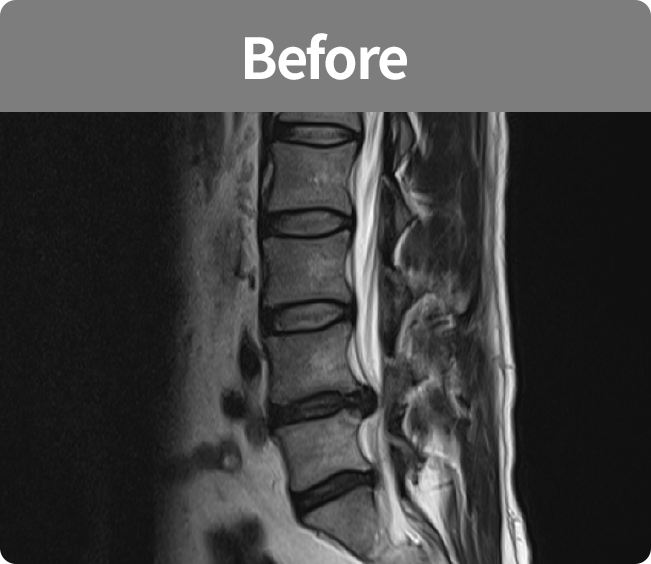

척추유합술

미세현미경을 통해 손상된 뼈와 인대조직을 제거하고 디스크의 역할을 해줄 인조 케이지를 삽입해

불안정한 척추체를 나사못으로 고정하는 수술 (척추 전방 골유합술, 척추 후방골유합술)